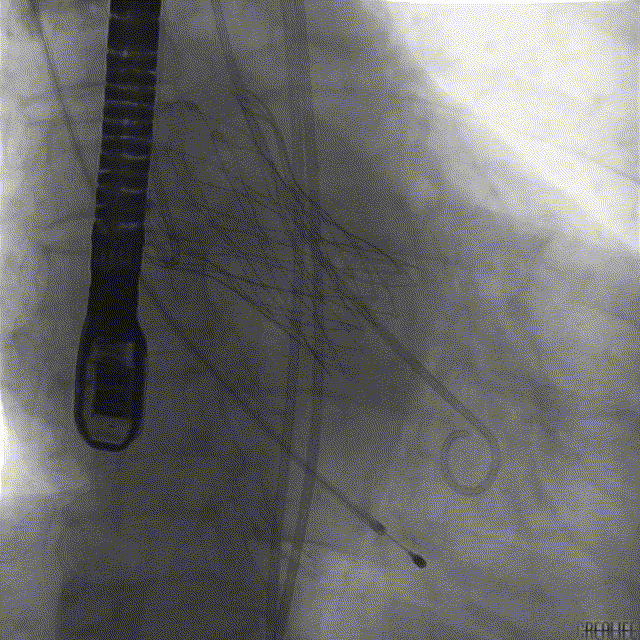

术中RCA示冠脉灌注尚可

窦底造影示反流明显

20mm球囊预扩无明显腰征

TaurusOne® 输送器顺畅过弓